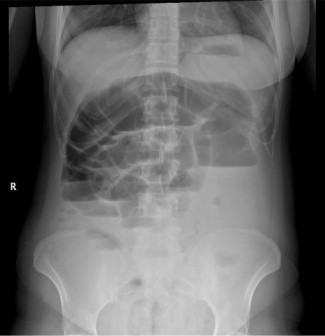

Απεικονιστικές εξετάσεις:

✅ Ακτινογραφία κοιλίας – Ανιχνεύει αέρια και διάταση του εντέρου